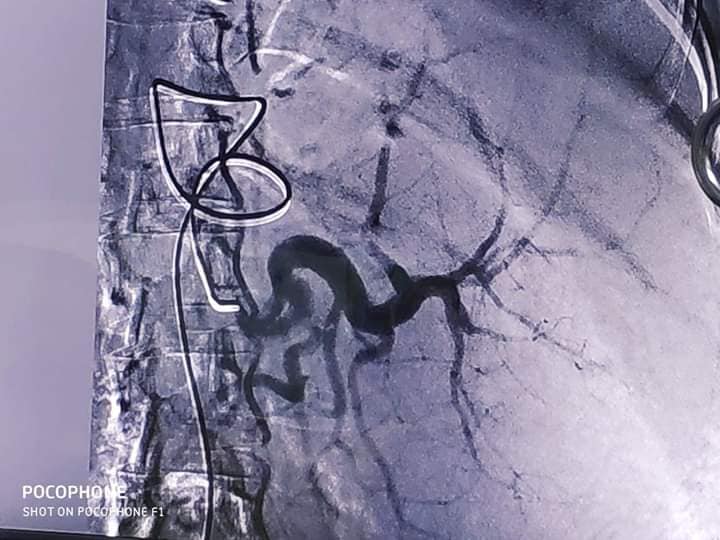

قسطرة علاجية لحقن وغلق شرايين الطحال النشط بمستشفي سوهاج الجامعي

اعلن قسم الاشعة التشخيصية والتداخلية بمستشفى سوهاج الجامعي عن نجاح اول حالة قسطرة علاجية لحقن وغلق شرايين الطحال النشط، وقال الدكتور احمد عزيز عبد المنعم رئيس الجامعة، ان هذا الاجراء يعد الاول من نوعه حيث يتم تطبيقه بالمستشفى الجامعى بهدف خدمة المجتمع السوهاجى وتقديم افضل خدمة طبية لهم .

واضافت دكتورة نهلة محمد على حسن رئيس قسم الاشعة بالمستشفى الجامعى ان هذا التدخل يعتبر بديل امن لعمليات استئصال الطحال جراحيا حيث يتم ادخال القسطرة من خلال فتحة صغيرة بالفخد يبلغ طولها ٢مم ثم توجيهها بالاشعة الى شرايين الطحال، وذلك باستخدام مخدر موضعى وبدون تدخل جراحى.